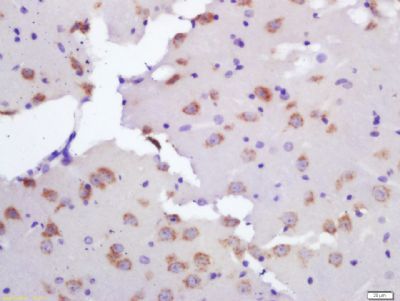

Ceramide synthase 2 Rabbit Polyclonal Antibody

ELISA, IF, IHC-Fr, IHC-P, WB

应用稀释比例:WB=1:500-2000, IHC-P=1:100-500, IHC-F=1:100-500, IF=1:100-500, ELISA=1:5000-10000